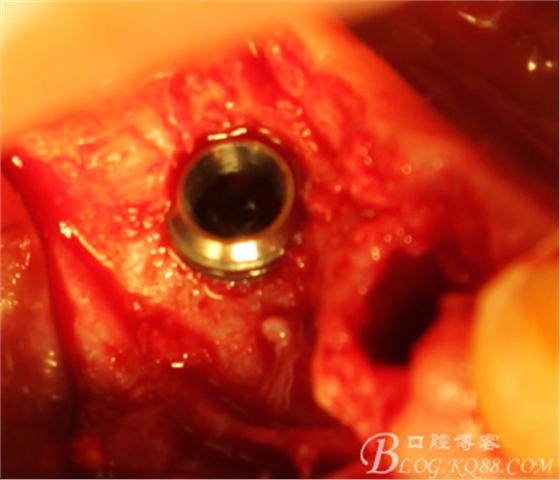

切開,成骨情況良好,

搔刮C5頸部肉芽

上愈合基臺,間斷縫合關(guān)閉創(chuàng)口,頰側(cè)牙齦部分恢復(fù)形態(tài)